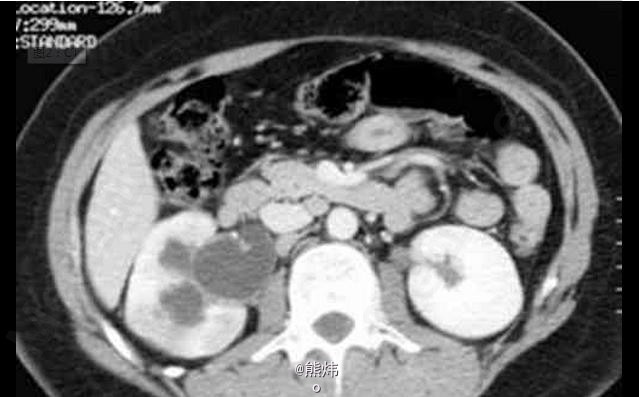

临床一例肾结核

肾结核

患者 女 30岁,因右腰疼痛1年前来就诊,既往无临床病史。

查:镜下血尿,尿培养阴性。伴有腰痛和发热 辅查造影

肾结核 处理:积极抗结核处理,采用链霉素